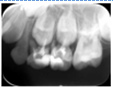

65MO深大龋洞,色棕黄,质软,叩痛(+),不松动,牙龈红肿,未见瘘管。 X线片示:冠部低密度影达髓腔,根分歧区大面积低密度影,近远中根内侧壁见吸收。25牙胚存,未拍全。 64MO深大龋洞,色棕黄,质软,叩痛(+),不松动,牙龈略红肿。 X线片示:根分歧区密度减低。 84OD深大龋洞,色棕黄,质软,叩痛(-),不松动, 85MO牙色充填体周围见龋坏,色黑,质软,叩痛(±),不松动,龈无异常。 X线片示:根周见低密度影,44,45牙胚存,未拍全。 54DOL深大龋洞,色黑,质软,叩痛(-),不松动, 55O窝沟色黑,卡探针,叩痛(-),不松动,龈无异常。 74OD,75MO半年前曾于外院行充填治疗,现检查见充填体边缘色黑,卡探针,充填体略有松动。

诊断:64,65,84,85慢性根尖周炎;54DOL深龋,55O中龋;74OD,75MO继发深龋 处置:64,65,84,85根管治疗 54DOL,55O行充填治疗 74OD,75MO去除旧充填体后充填治疗

乳牙根管治疗术是治疗乳牙根尖周病的有效方法,通过根管预备和药物毒去除感染物质对根尖周组织的不良刺激,并用可吸收的充填材料充填根管,促进根尖周病愈合。 在第一恒磨牙未完全萌出之前,为防止乳牙早失造成第一恒磨牙近中移位,对于第二乳磨牙的较大面积根尖周病变我们采取保守治疗,根管治疗后需定期复查,一旦发生病变扩大及时拔除,在此病例中第一恒磨牙未完全萌出,我们对65,85进行试保留,半年后临床检查无异常,x线片显示病变较初诊时缩小,建议继续观察。